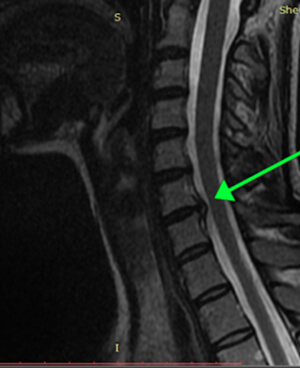

Резорбция грыж — это терапевтический процесс, направленный на уменьшение или полное исчезновение межпозвонковых грыж без хирургического вмешательства. Данный метод включает серию около 12 посещений клиники, три раза в неделю. После курса процедур, врач определяет время контрольного МРТ (обычно 2-3 месяца) для оценки результатов лечения.

Не все грыжи поддаются лечению данным методом. Решение о назначении резорбции принимается на основе анализа жалоб пациента, результатов МРТ и срока давности грыжи. Метод является безопасным и отличается отсутствием осложнений.

Кейс 2